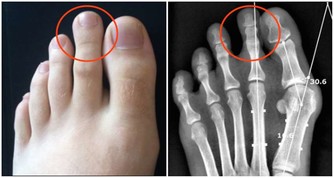

亞健康,身體都會出現哪些症狀?

亞健康人群,往往以疲勞、睡眠紊亂、疼痛等症狀表現為主,常伴有記憶力下降、注意力不集中、思維緩慢、反應遲鈍等情況。

亞健康人群進行抽血、CT、磁共振等各種檢查,未必能查得出什麼問題。如果進行“中醫體檢”,卻往往能發現氣血虧虛。